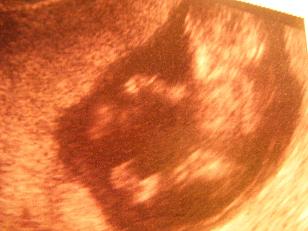

Minden rendben, bár ismét kisebbnek látta babócát, azt mondta 8-9 hetesnek látja, a kiskönyvembe 9 hetest írt. Viszont láttam a picikém gömbölyü buksiját és integetett nekem :):):):):):):):)